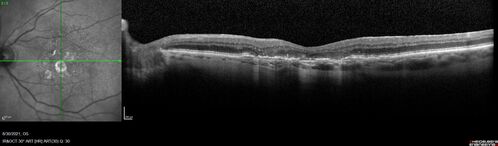

Pigment migration in dry age-related macular degeneration

80 year old female. Dry AMD with GA in the left eye and pigment migration visible on OCT scan.

VA 20/40 OD, 20/160 OS